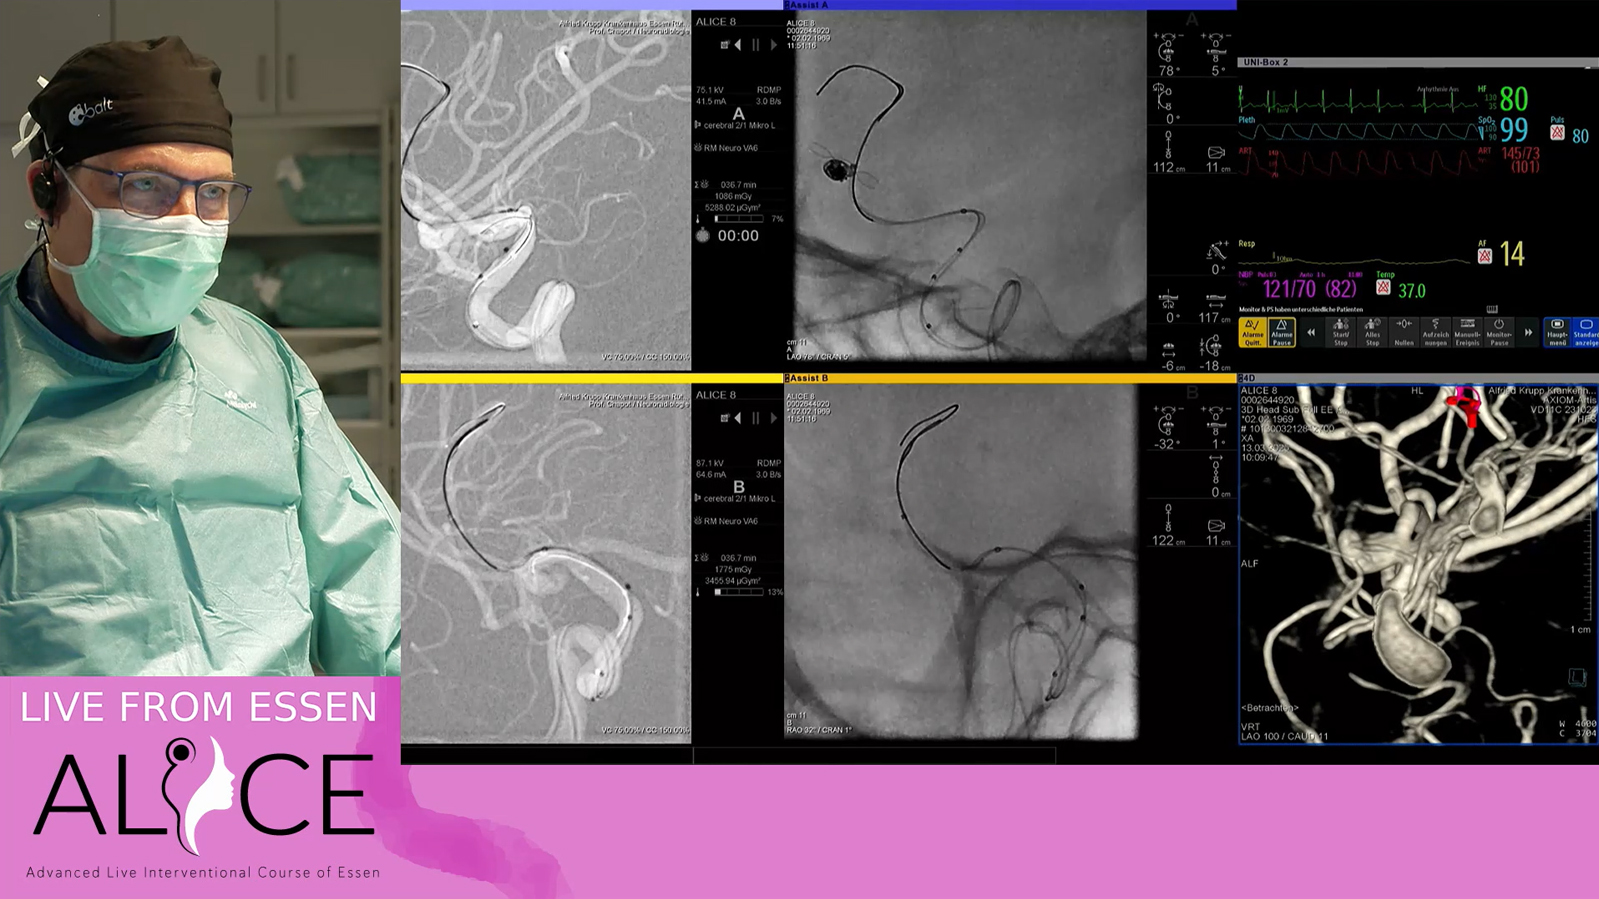

MCA aneurysm treated by double balloon assisted coiling followed by Stenting with Baby Leo